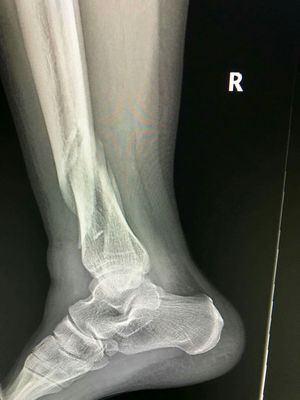

Xray

Fracture

Ankle